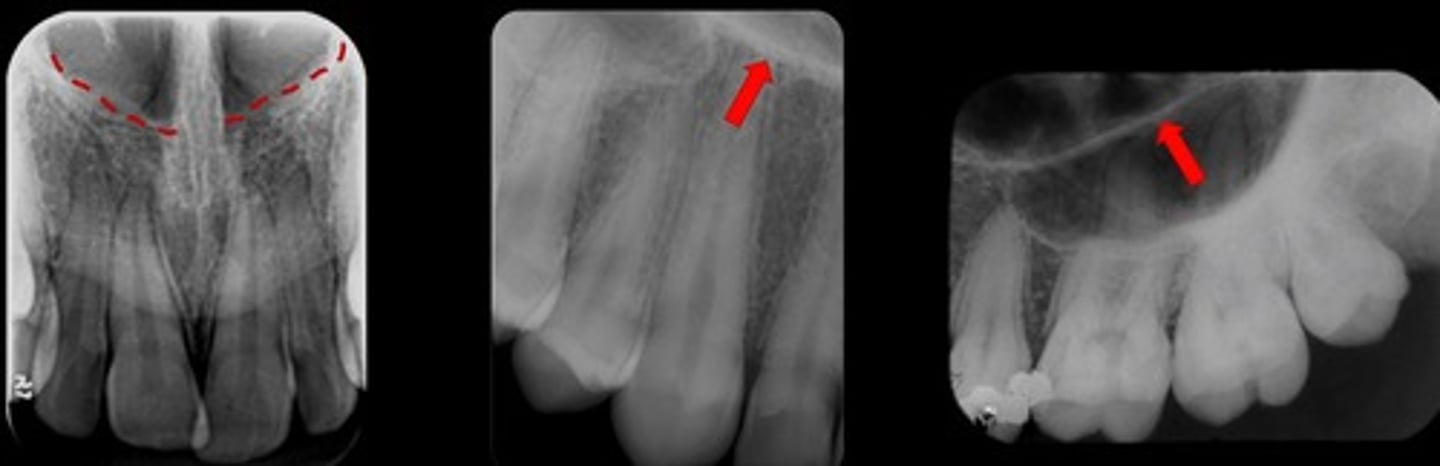

Hypercementosis

What are the red arrows representing?

What are the red arrows pointing to?

Alveolar crest

Nasal cavity - nasal fossae

What are the red dotted lines circling?